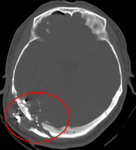

Occipital fracture extending to foramen magnum: risk of brainstem compression by hematoma

From the teaching collection of Demetrios Demetriades; used with permission